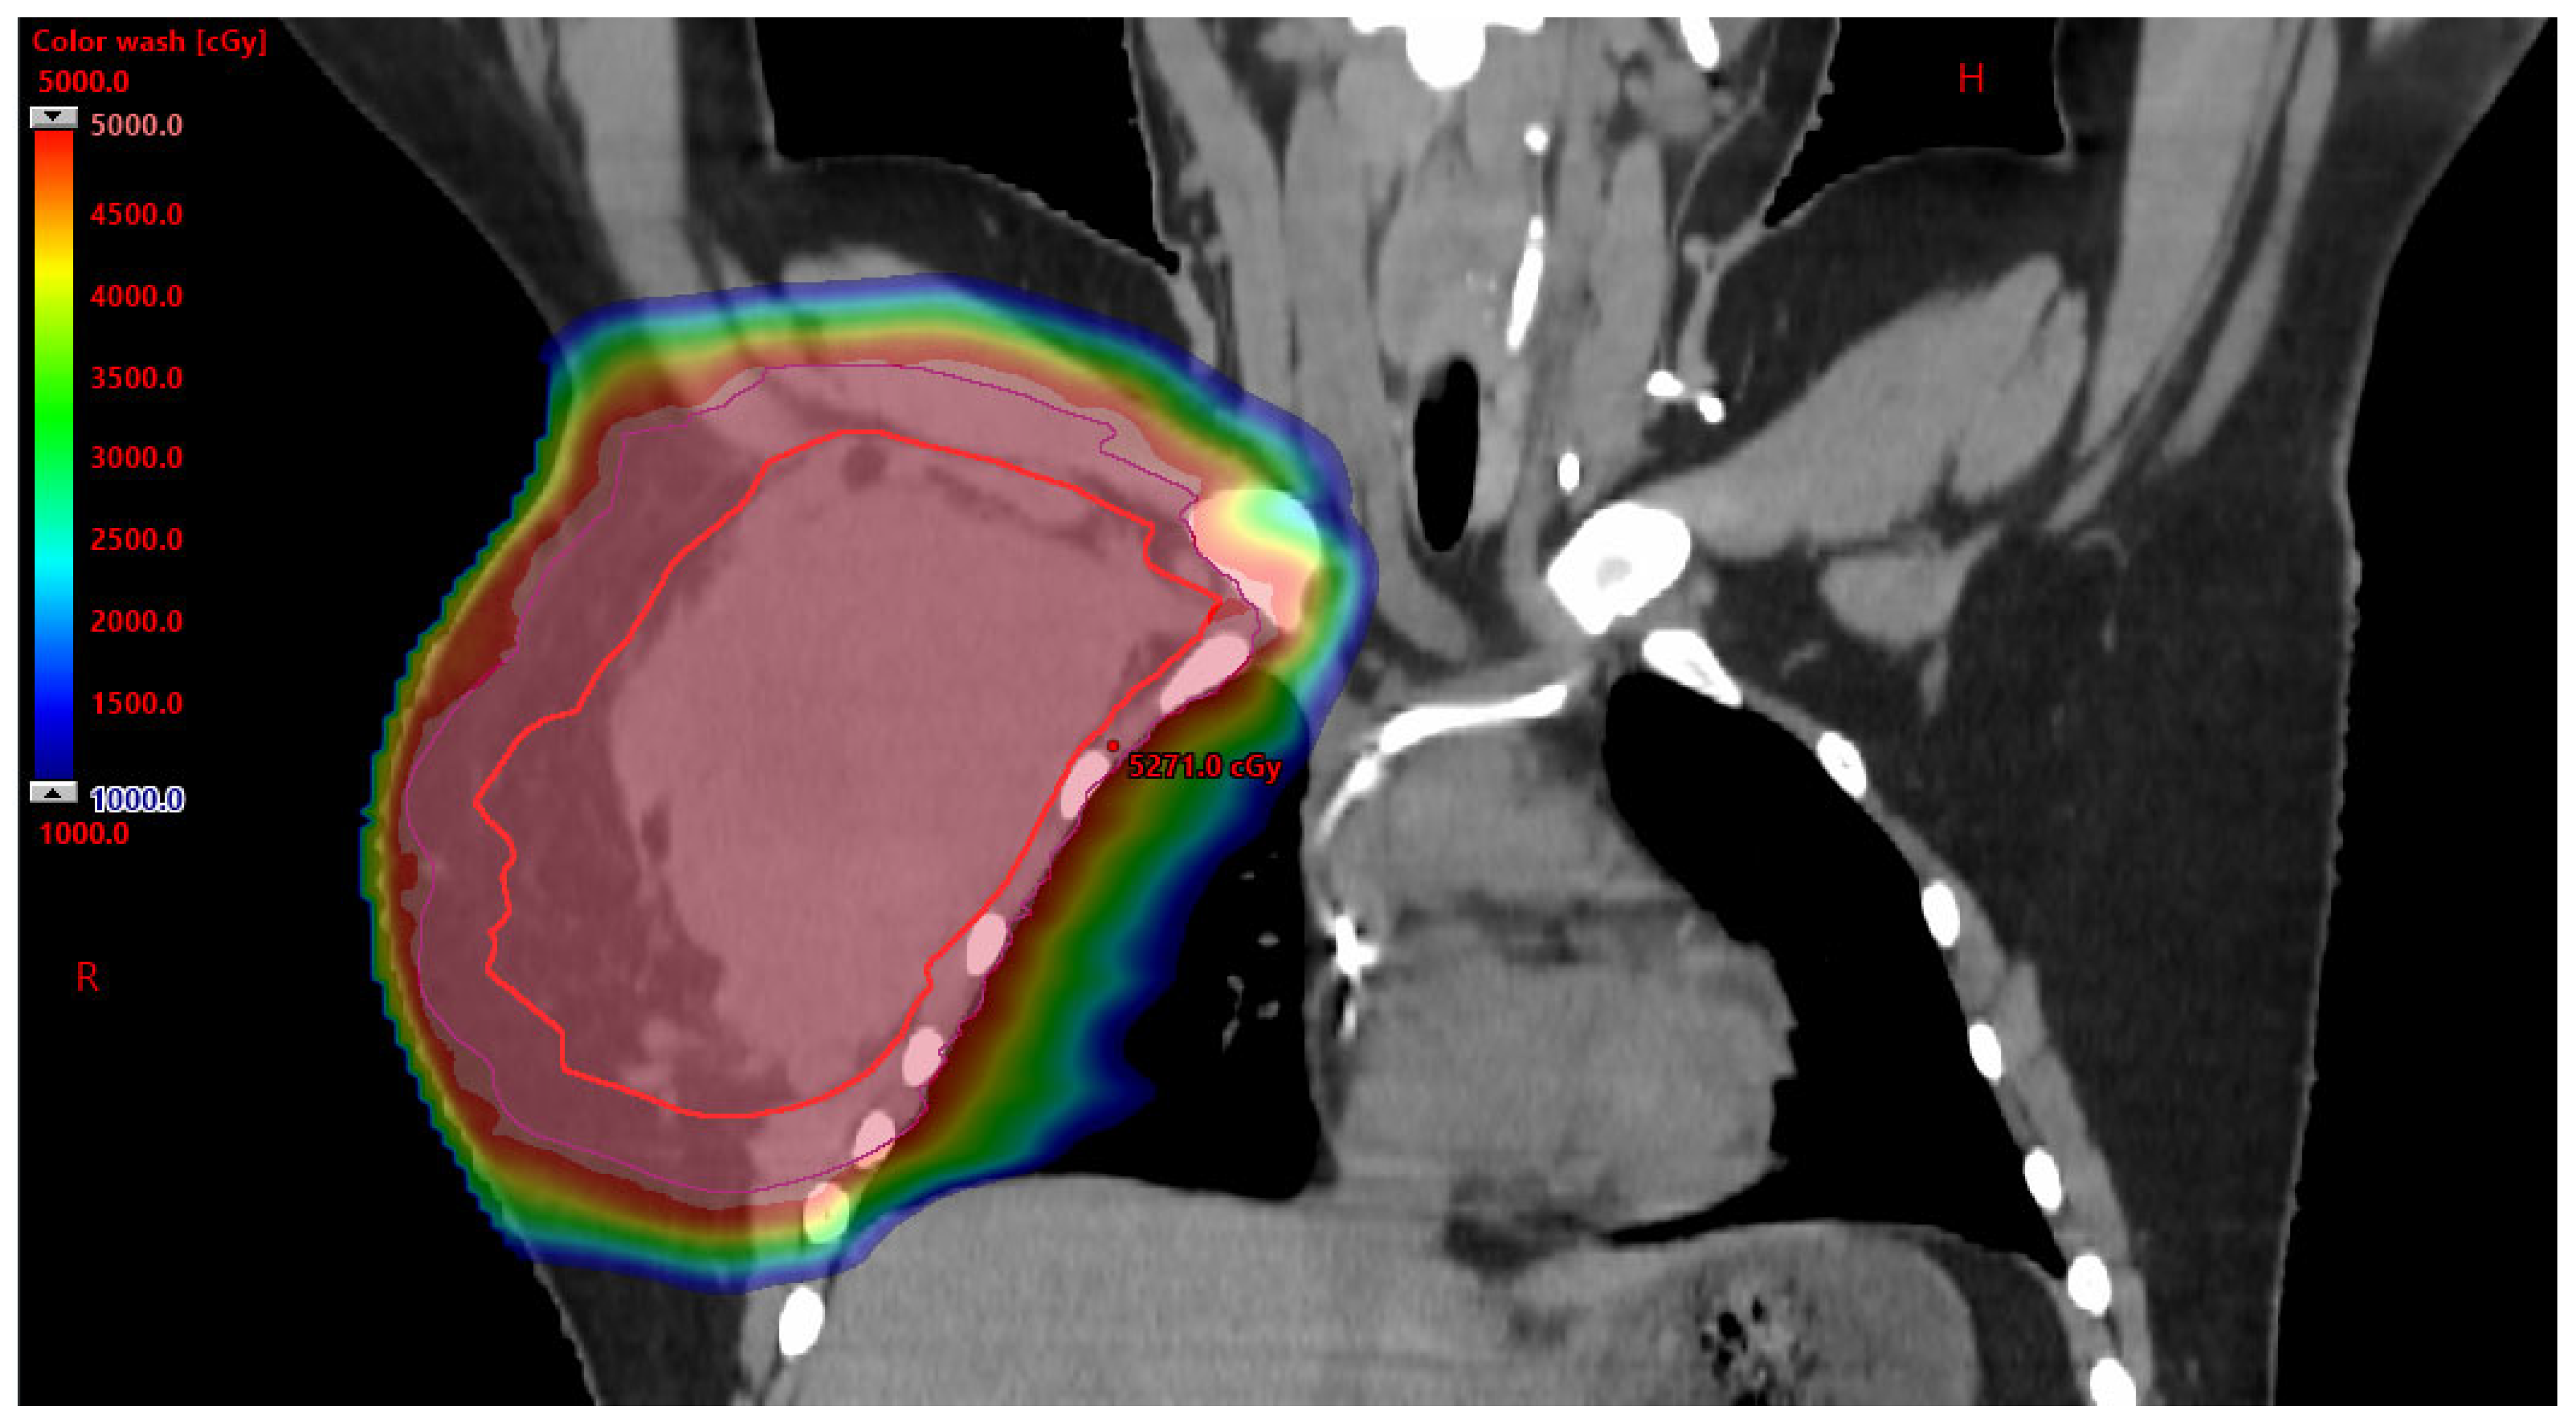

3.2.1. Benefits to PBT